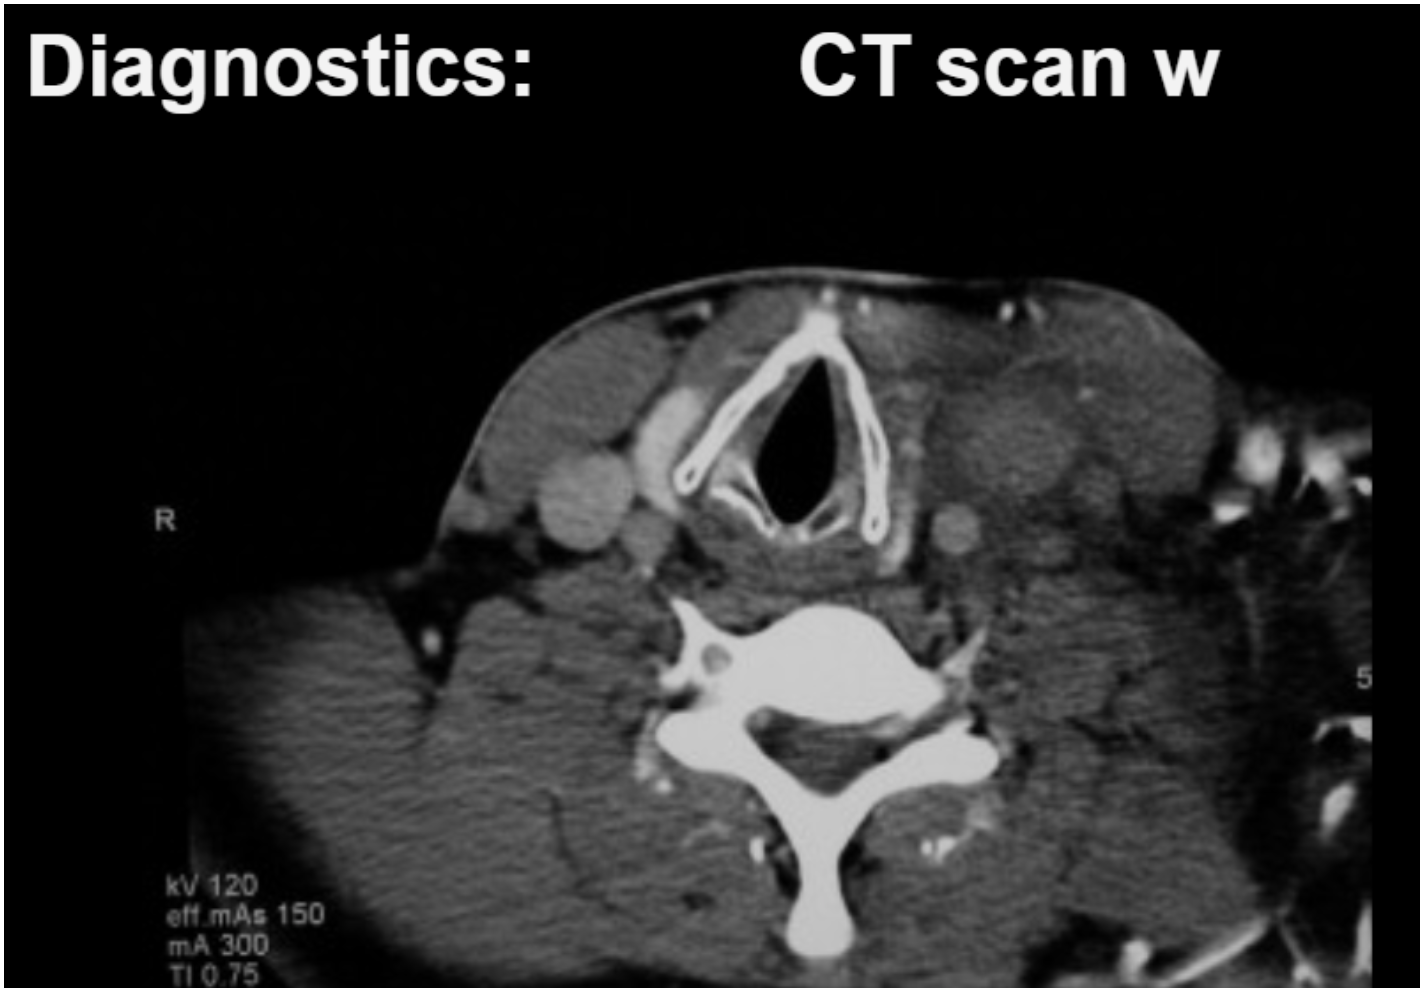

CT of the neck confirms a right IJ clot.

To make the diagnosis, we need a CT (or ultrasound) of the neck, looking for evidence of an IJ clot.